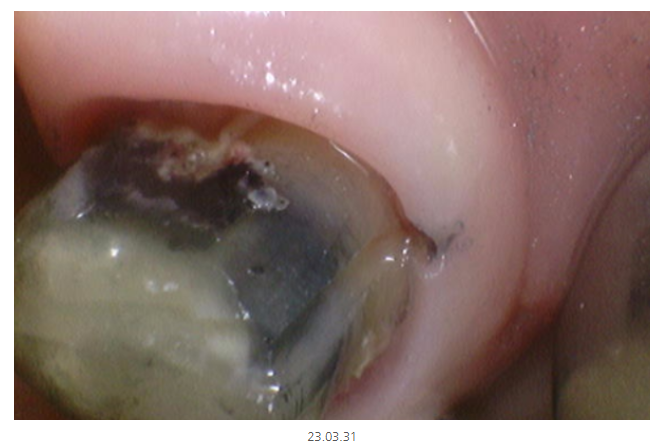

해당 환자분은 보철을 벗겼더니

충치가 있는 것을 찍어둔 사진입니다.

치아 상태가 이래서 치료를 할 수 밖에 없었다

최대한 자세히 설명드리고 싶거든요~